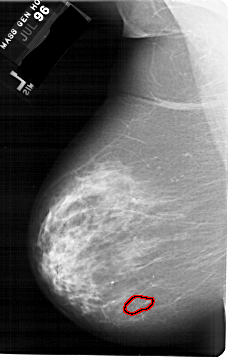

A_1774_1.RIGHT_CC

RIGHT_CC LINES 6871 PIXELS_PER_LINE 3991 BITS_PER_PIXEL 12 RESOLUTION 43.5 NON_OVERLAY

FILE: A_1774_1.LEFT_CC.OVERLAY

TOTAL_ABNORMALITIES 1

ABNORMALITY 1

LESION_TYPE CALCIFICATION TYPE PLEOMORPHIC DISTRIBUTION CLUSTERED

ASSESSMENT 4

SUBTLETY 1

PATHOLOGY BENIGN

TOTAL_OUTLINES 1

BOUNDARY